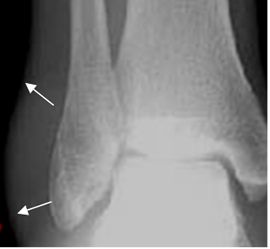

La Rx puede ser normal o mostrar edema de tejidos blandos. (12). (Fig 58 A y B).

Fig 58 A. Esguince del tobillo.

Rx AP. Edema de tejidos blandos, sobre el maléolo externo.

Fig 58 B. Edema de tejidos blandos.

A y B: TAC reconstrucción coronal en ventana de tejido y ósea. Prominencia de los tejidos blandos en la parte externa, con pérdida de los planos grasos, por edema.

C: RM axial en STIR y D: RM coronal en T2. Edema de tejidos blandos hiperintenso en ambas secuencias, con pequeña colección líquida. (Flecha gruesa).